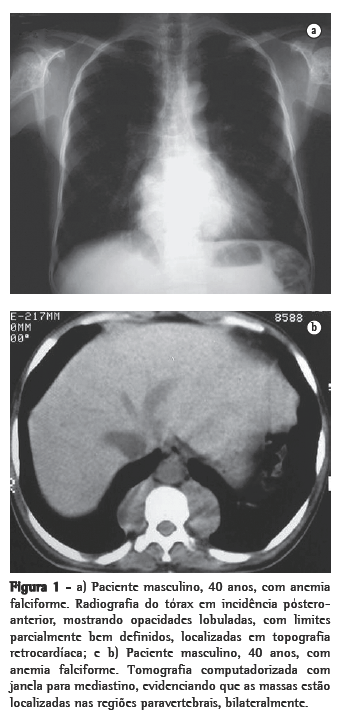

Os outros dois pacientes mostravam massa parietal e pleural, ambas à esquerda, sem evidência de comprometimento paravertebral. Em um desses, a massa era homogênea (Figuras 3a e b); no outro, havia reação óssea associada.

Como achados associados, dois pacientes mostravam calcificações no baço (Figura 4). Ambos eram portadores de anemia falciforme. Dos seis pacientes, dois haviam sido esplenectomizados, e em dois a imagem do baço era normal. Alterações ósseas relacionadas à doença de base foram identificadas em três pacientes.

Todos esses aspectos foram identificados em nossos casos. É interessante ressaltar que os achados em dois pacientes mostravam calcificações no baço, decorrentes de infartos múltiplos, com autoesplenectomia. Ambos eram portadores de anemia falciforme. Esse achado pode também auxiliar no diagnóstico diferencial.